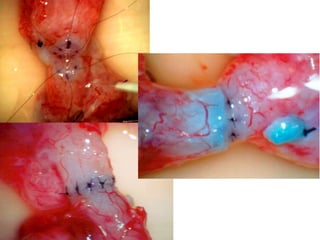

Protruding tubule Inking tubule

Tunica Incision

Dilated tubule

Protruding tubule Inkingtubule Tunica Incision Dilated tubule